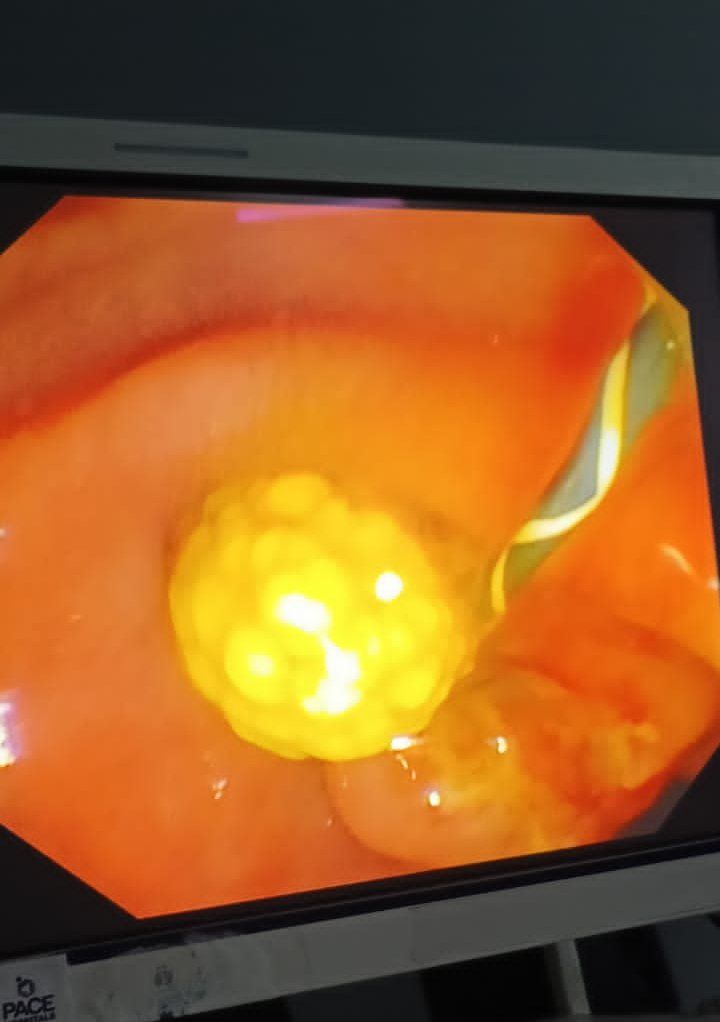

ERCP with pancreatic duct stent placement for chronic pancreatitis patients

20 year young man is a known case of early idiopathic chronic pancreatitis. The patient was admitted with complaints of recurrent upper abdominal pain radiating to the back, with inability to gain weight. Patient underwent ERCP. Pancreato-gram taken suggested dilated PD throughout the head and body, with multiple intraductal pancreatic stones. Balloon sweeps were taken with removal of multiple small white, shiny pancreatic stones. 7 Fr x 10 cm pancreatic stent was inserted. Post procedure there was a significant improvement in the patient’s quality of life with no recurrent pain episodes and weight gain.

Conclusion:

ERCP with PD stenting can improve symptoms in the select group of patients with chronic pancreatitis.